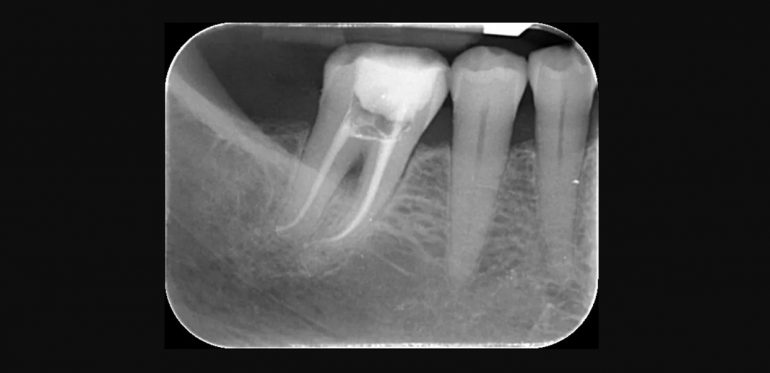

- sigillatura tridimensionale di tutte le strutture del canale (compresi canali laterali e delta apicale) tramite una gomma termoplastica (guttaperca) ed un cemento canalare autoindurente, secondo le tecniche di condensazione laterale a freddo, o condensazione verticale a caldo.

- controllo radiografico.